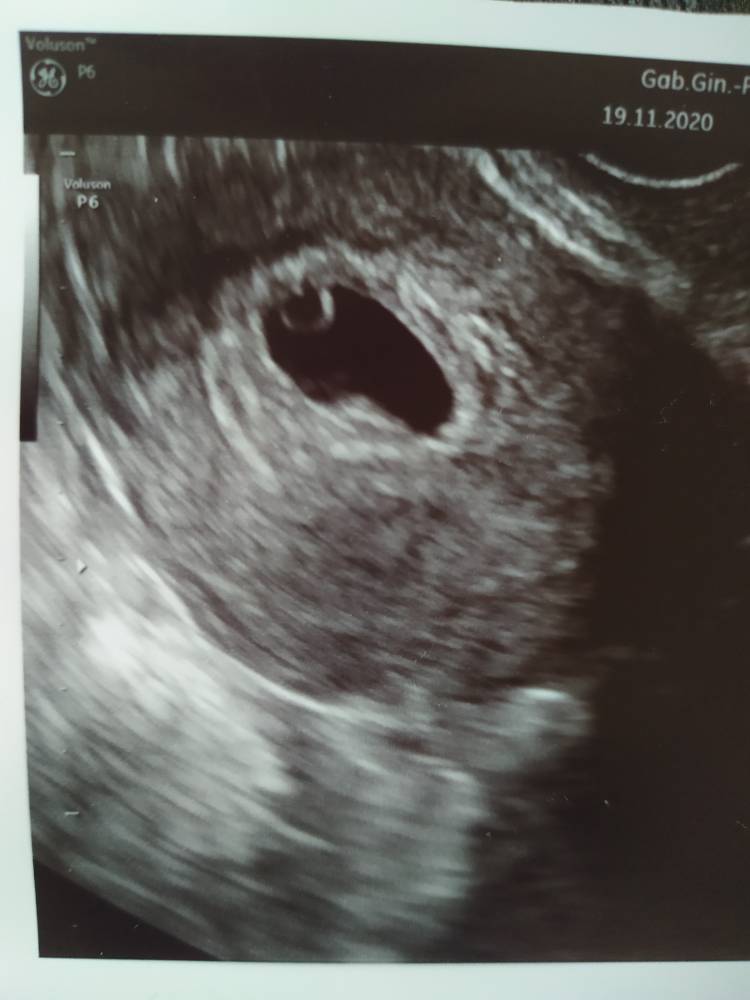

19.11: @kolor nadzieji - 1 USG[emoji110][emoji110][emoji123][emoji123]

19.11: @Claudii - 1 USG[emoji110][emoji110][emoji123][emoji123]